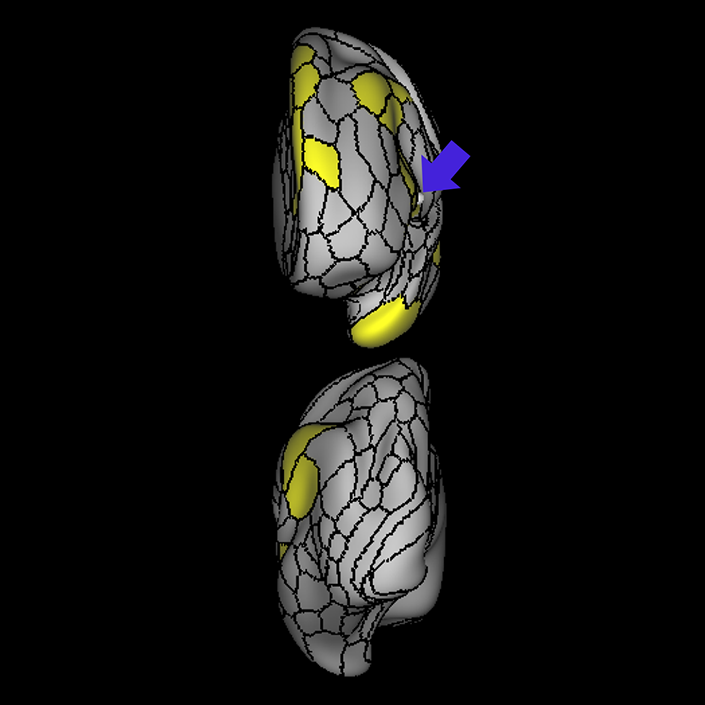

ᐅ SummaryArea 45: part of the inferior frontal gyrus of the lateral frontal lobe. In addition to its known association with Broca's area, is sometimes represented as part of Broca's complex ᐅ Where is it?Area 45 is the lateral surface of pars triangularis of the IFG. ᐅ What are its borders?Area 45 borders area 47L anteriorly and area 44 posteriorly. Its superior edge borders area p47r, IFSa, and IFSp. Its opercular surface is conveniently named FOP5 ᐅ What are its functional connections?Area 45 demonstrates functional connectivity to areas SFL, IFSp, 44, a47r, 47s, 47L, 9a, 9p, 9m, 8AV, and 8BL in the dorsolateral frontal lobe, area 8BM in the medial frontal lobe, area 55b in the premotor areas, areas FOP5, and PSL in the insula-opercular region, areas TGd, TGv, TE1a, STSva, STSdp and STSvp in the temporal lobe, area PGi in the inferior parietal lobe, and area 31pd in the medial parietal lobe. ᐅ What are its white matter connections?Area 45 is structurally connected to the arcuate/SLF and IFOF. However, arcuate/SLF connections are not consistent across individuals. Connections with the arcuate/SLF project posteriorly and wrap around the Sylvian fissure to the middle temporal gyrus to end at TE1p. There are also projections from the arcuate/SLF before it terminates to parcellations A4 and PBelt. IFOF connections travel from 45 through the extreme/external capsule and continue posteriorly through the temporal lobe to end at occipital lobe parcellations V1, V2, V3 and V4. Local short association bundles connect with 44 and FOP4. ᐅ What is known about its function?Area 45, in addition to its known association with Broca's area, is sometimes represented as part of "Broca's complex", including Brodmann Areas 45, 46, 47 and the mesial supplementary motor area of 6, which contribute to a frontal-subcortical circuit. |

A: lateral-medial

B: anterior-posterior

C: superior-inferior

DTI image |